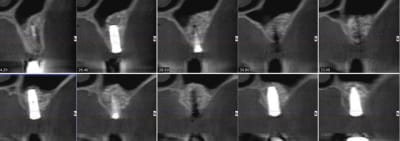

pour illustrer cette utilisation du bioactys, voici un cas (ce matin, mise en focntion des implants à 7 mois post_op)

pour la pose immédiate, çà dépend aussi du type d'implant utilisé...ici c'est des superline dentium...;-)

ils ont vraiment une super stab primaire, et leur design est parfait pour les zones sous sinusienne...entre autre....parce que pour l'instant, mis à part le manque d'un repère visible sur le préhenseur de la position de l'hex antirotationnel, j'ai pas encore trouvé de défaut au système...

ici c'est un mix (pour un impératif perso): en 25 un easy-implant master s puis 2 dentium superline.

j'ai donc procédé à la mise en fonction ce matin, 7 mois après l'intervention. Mise en place de piliers de cicatrisation assez hautes et surtout de diamètres en adéquation avec une PM et 2M. je prends l'empreinte dans 3 semaines , la gencive sera belle autour des piliers.